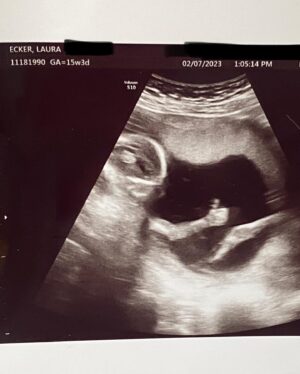

Caption : i still can’t believe my future best friend is just chillin’ in thereLikes : 3806

Caption : i still can’t believe my future best friend is just chillin’ in thereLikes : 3806